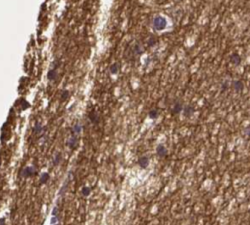

SMIM17 - a `Gene Doe` of the brain

Among the about 20,000 genes giving rise to the human proteome there are still many rather unknown but potentially interesting genes that deserve some extra attention. Here we will focus on SMIM17, a gene with little evidence and specific expression in the brain...Read more